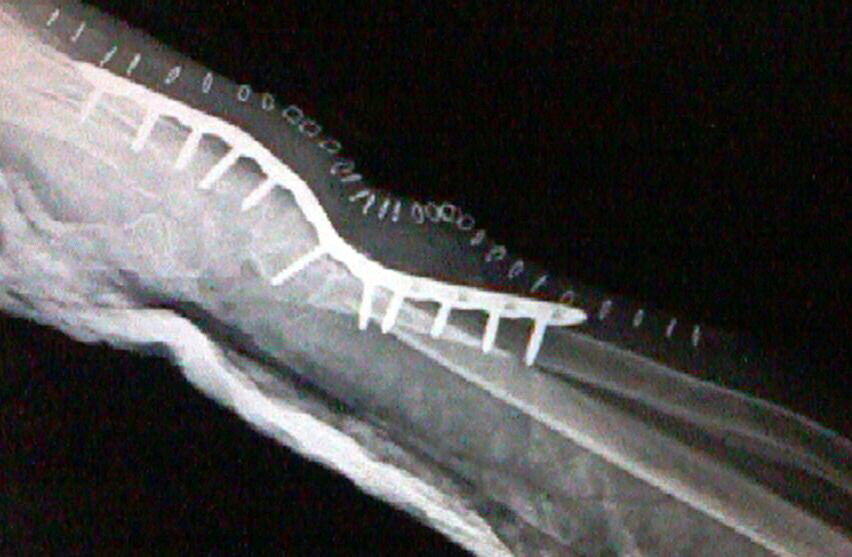

Wrist Deformity Correction